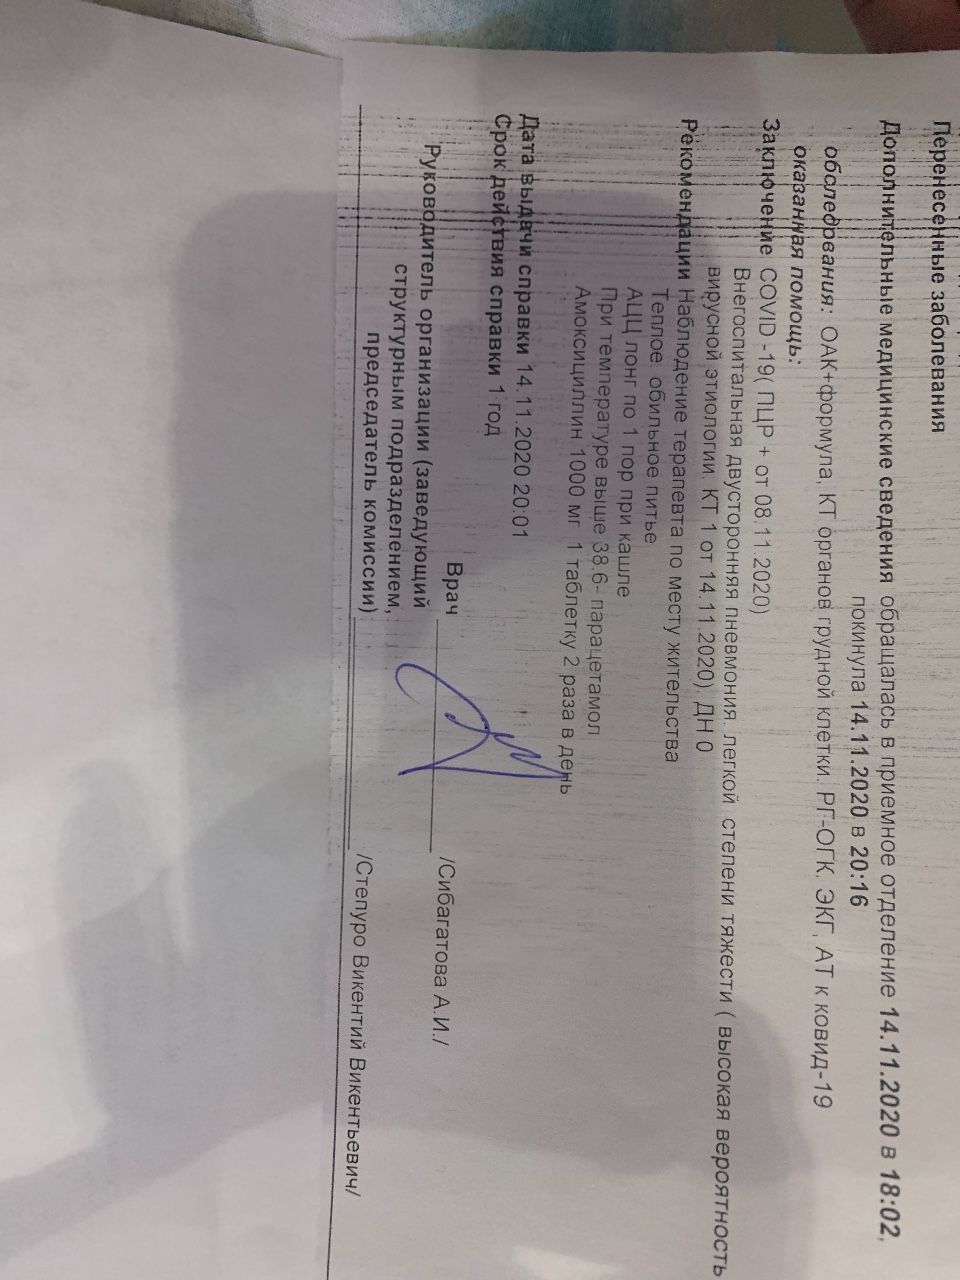

Острая внебольничная пневмония по МКБ-10: признаки и примеры